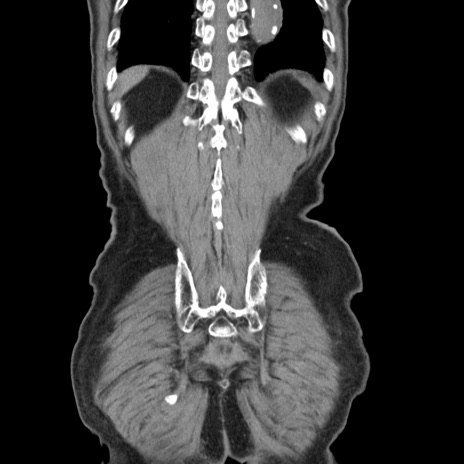

症例24(冠状断像)

【症例】80歳代男性

【主訴】左側腹部痛、嘔吐

【現病歴】本日早朝より左腹部に痛みあり。昼頃嘔吐認めたため、救急要請。

【既往歴】直腸癌(Mile手術)、胆摘

【身体所見】意識清明、BT 35.9℃、BP 221/93mmHg、SpO2 97%(RA) 、腹部:左ストーマ周囲に限局性の腹部膨隆あり。 膨隆部自発痛・圧痛あり・軟。

【データ】WBC 7700、CRP 0.09